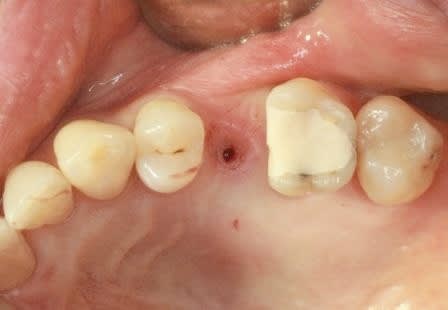

Serrage manuel, sans lambeau. Extraction implantation immédiate

le 4.5*11 me semblait convenable. J'avais peur que si je metais du 4*11 l'espace entre les cretes vestibulaires et l'implant allait creer une recession si je ne comblait pas ce vide

Rappelons qu'en mesurant j'ai 1.25 mm d'os au final et pas 0.5-0.8mm

merci pour tes réponses, pour ma part (expérience avec plus de 600 implantation immédiate) je ne pense pas qu'il va y avoir une résorption, car pas de lambeau et tu n'as pas mis de trop grande pression sur l'os buccal.Un exemple ci dessous implantation ( 4 semaines après extraction) avec un 4.5 que (oui déjà mis dans un autre post).J'ai d'autres exemples similaires en extraction implantation immédiate mais avec des implants 3.5mm.Si l'espace entre l'implant et l'os buccal est plus grand que 1mm j'ajoute du collagène et de l'acide hyaluronique pour accélérer la régénération.

dernière radio à un an après cémentation de la couronne.

Ce qui est non négligeable est d'avoir une stabilité primaire d'un minimum de 35Ncm et pas plus de 70Ncm.